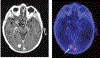

Despite major therapeutic advances in the management of patients with breast cancer, central nervous system (CNS) metastases remain an intractable problem, particularly in patients with metastatic HER2-positive and triple-negative breast cancer. As systemic therapies to treat extracranial disease improve, some patients are surviving longer, and the frequency of CNS involvement seems to be increasing. Furthermore, in the early-stage setting, the CNS remains a potential sanctuary site for relapse. This review highlights advances in the development of biologically relevant preclinical models, including the development of brain-tropic cell lines for testing of agents to prevent and treat brain metastases, and summarizes our current understanding of the biology of CNS relapse. From a clinical perspective, a variety of therapeutic approaches are discussed, including methods to improve drug delivery, novel cytotoxic agents, and targeted therapies. Challenges in current trial design and endpoints are reviewed. Finally, we discuss promising new directions, including novel trial designs, correlative imaging techniques, and enhanced translational opportunities.